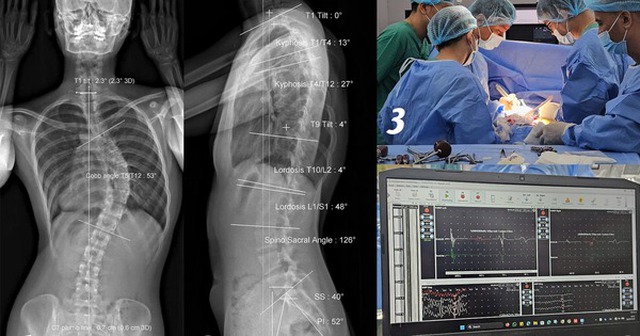

Hình ảnh EOS cho thấy người bệnh vẹo cột sống ngực 53 độ. Sau đó, các bác sĩ tiến hành phẫu thuật cùng với hệ thống IOM cảnh báo thần kinh trong phẫu thuật cột sống.

Tại đây, D. được chụp EOS (chụp quang tuyến thấy toàn bộ trục xương của cơ thể) và thăm khám. Kết quả cho thấy cột sống cô bị vẹo 53 độ, mức độ nghiêm trọng, có nguy cơ ảnh hưởng đến thẩm mỹ, tâm lý và chức năng vận động nếu không được điều trị kịp thời.